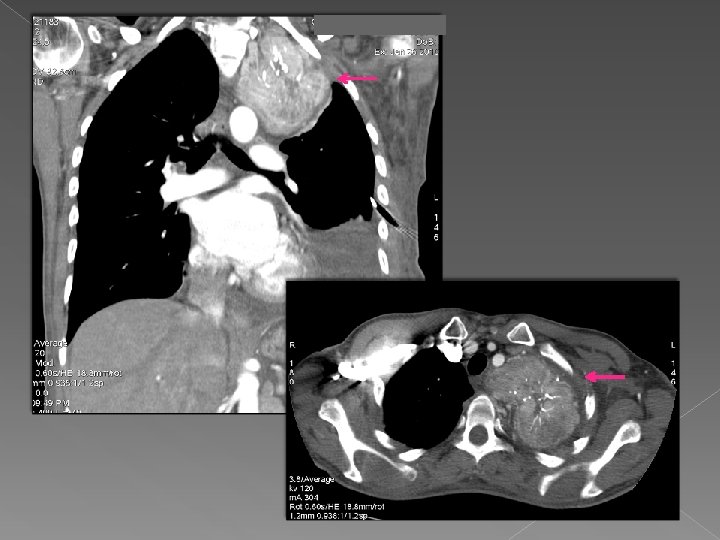

Caso 3 Mujer de 39 años con una tumoración extrapulmonar de gran tamaño, hipervascular

Caso 3 Mujer de 39 años con una tumoración extrapulmonar de gran tamaño, hipervascular con calcificaciones en su interior en vértice de hemitorax izquierdo diagnosticado de Tumor Castleman tras anatomía patológica. Valor del VR: nos aporta valiosa información sobre la morfología que adopta sobre todo de cara a la intervención quirúrgica.